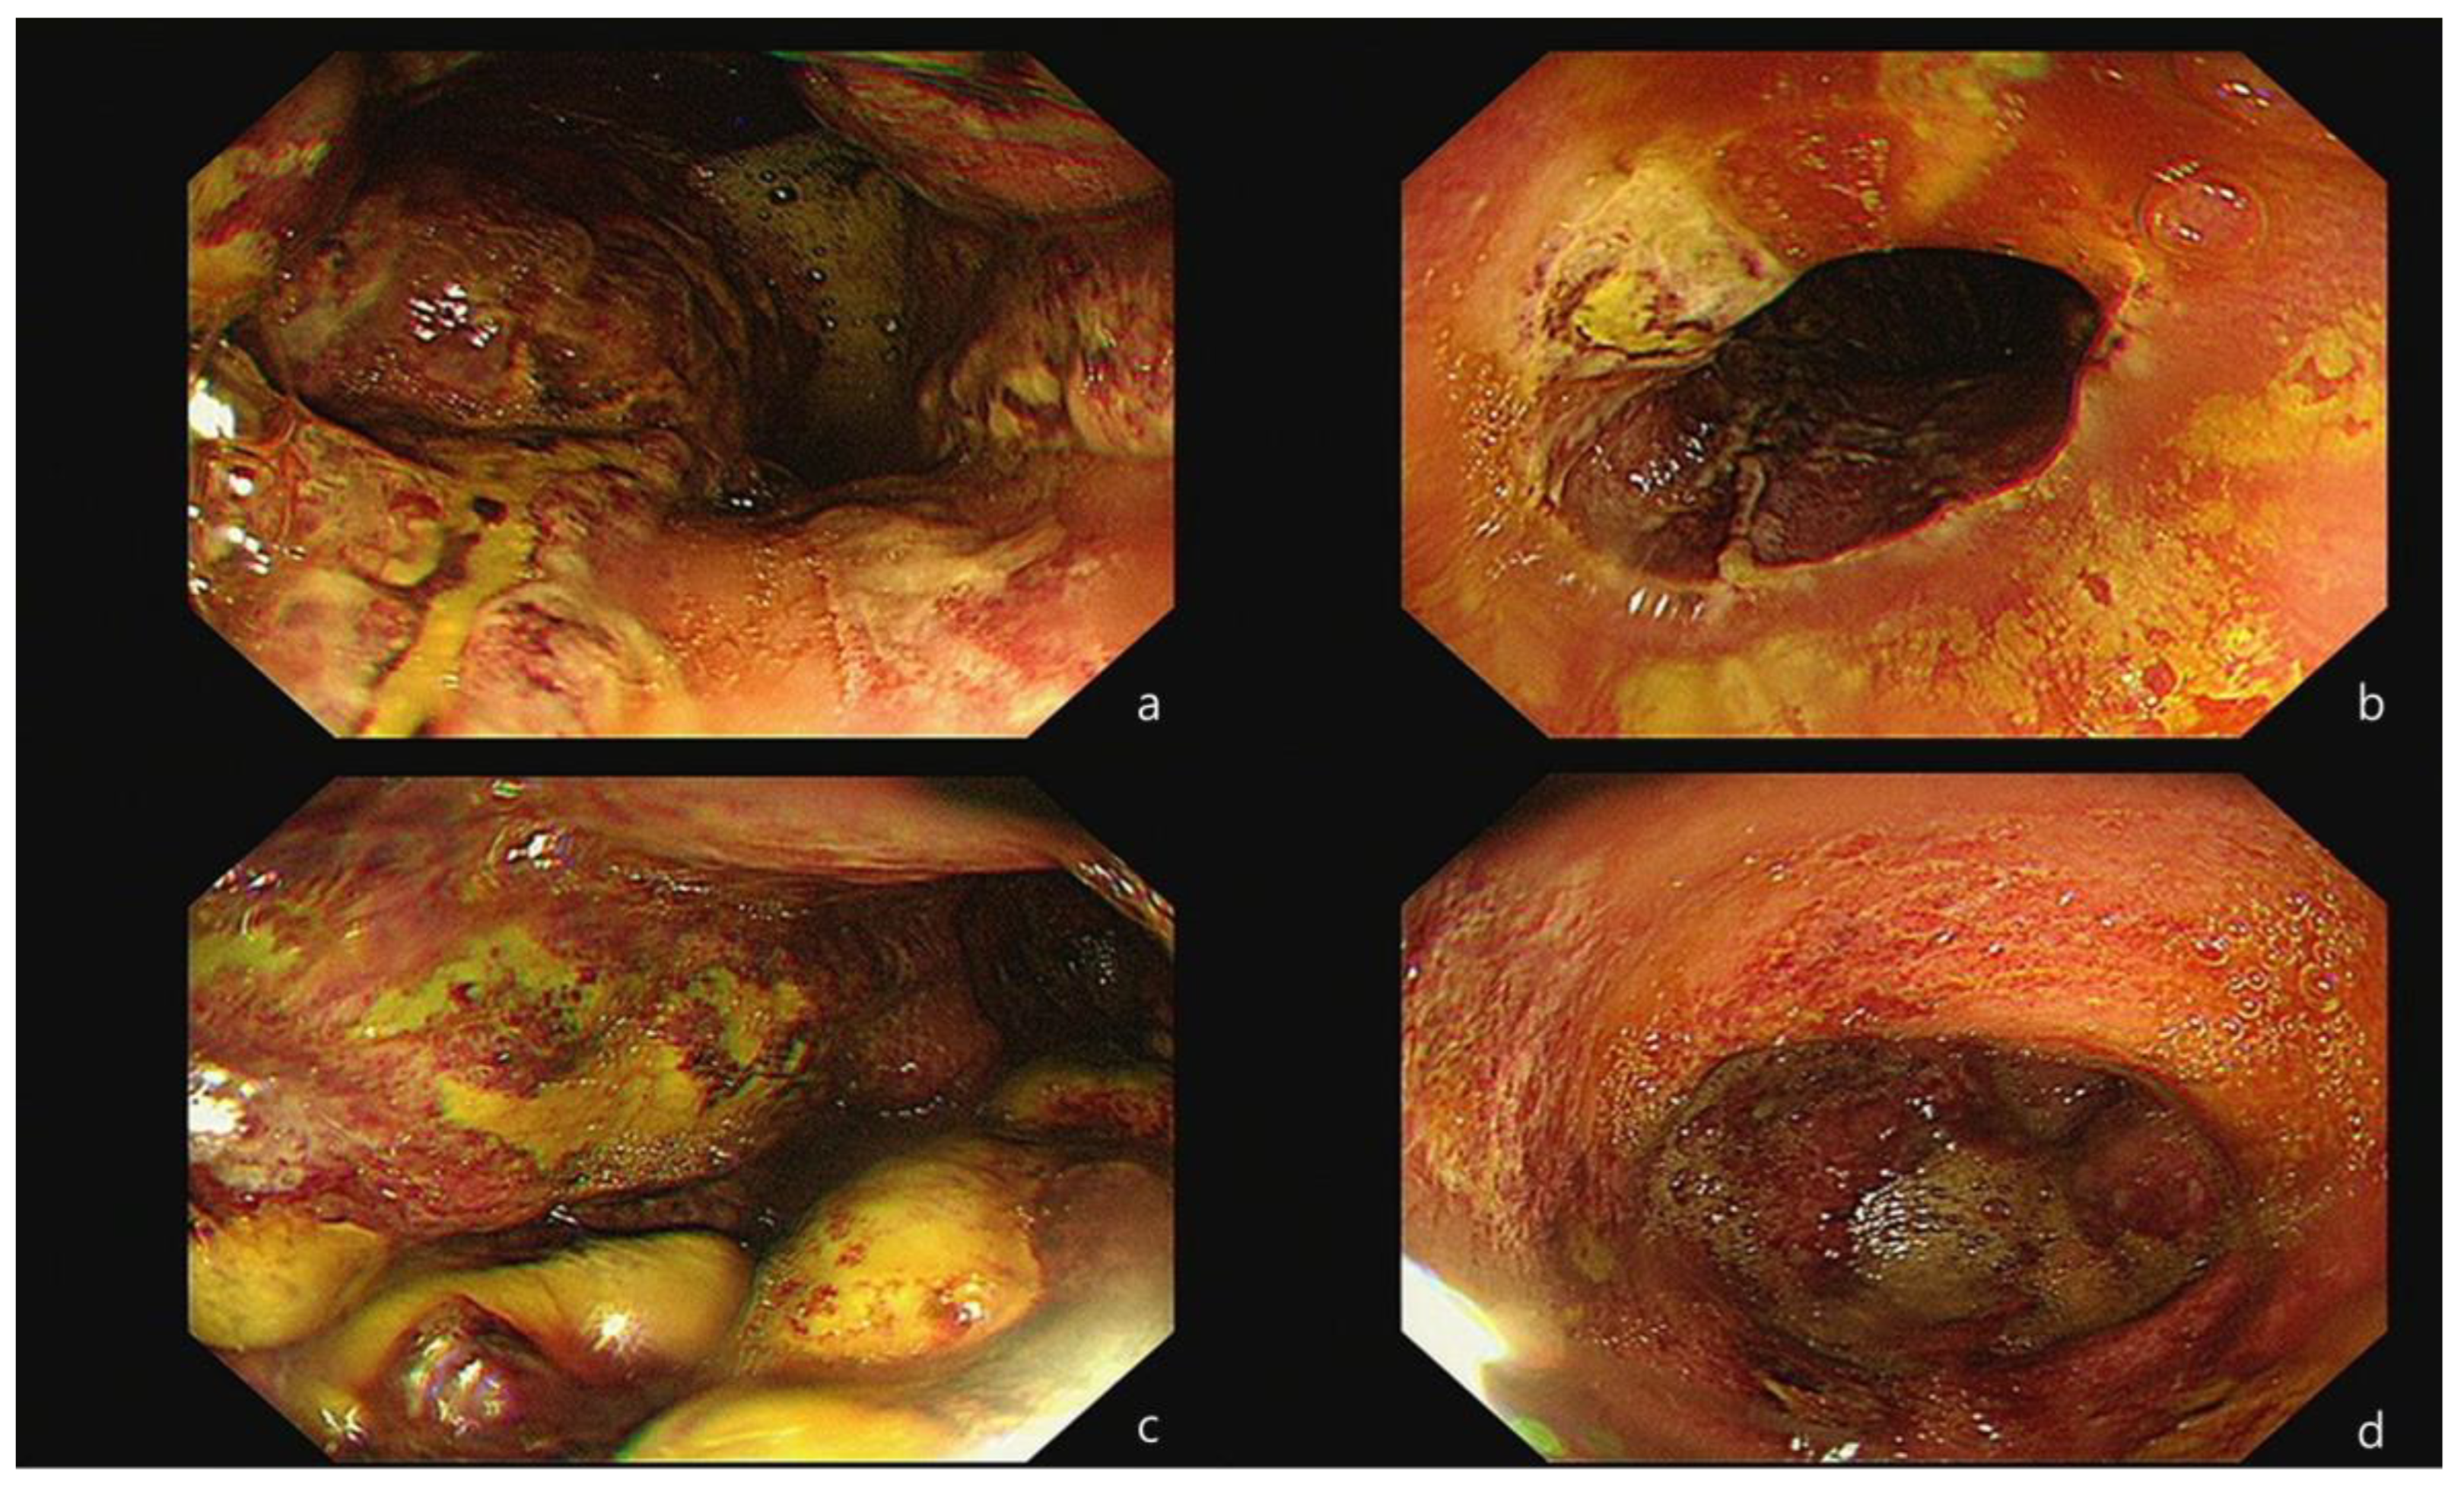

Because the bloody vomiting continued occasionally until the next morning, an esophago-gastro-duodenoscopy (EGD) was performed, under consultation, to identify the source of the ongoing bleeding and to assess the severity of the intestinal injury. The procedure revealed a thick exudate with linear ulceration and hemorrhagic spots in the lower esophagus. Additionally, extensive necrosis and multiple ulcerations with brown-grayish discoloration were observed throughout the entire stomach (Figure 2). As a result, the patient was diagnosed with corrosive gastritis, grade IIIB. A decision was made to admit her and to maintain an NPO (Nil Per Os) status until she was re-evaluated for the resumption of a normal diet. Throughout this period, her vital signs remained consistently stable.

Figure 2. Initial endoscopic test results. The first endoscopic test was performed approximately 20 h post-ingestion. A thick exudate with linear ulceration and hemorrhagic spots were noted in the esophagus (a,b). Extensive necrosis and multiple ulcerations with brown-grayish discoloration were observed across the whole stomach (c,d).